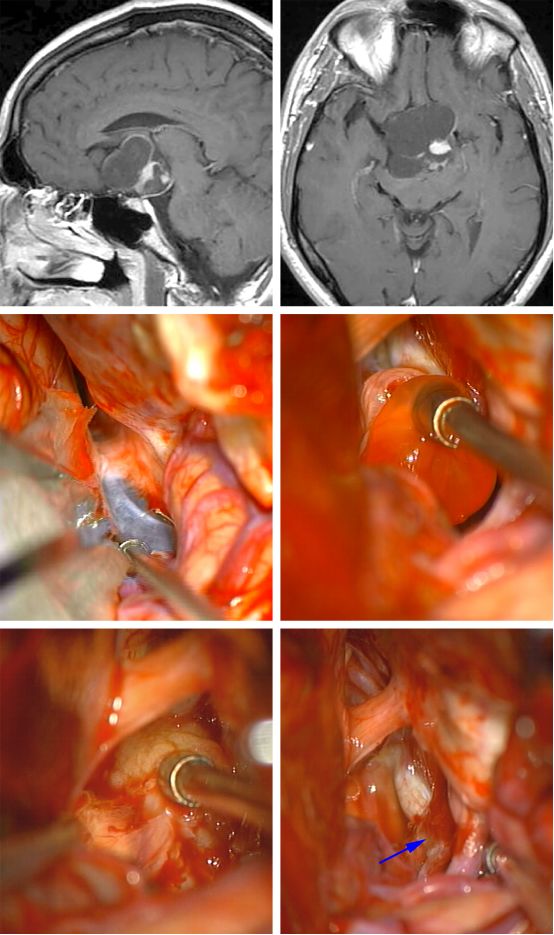

图7. 一个视交叉前方的囊性颅咽管瘤(第一排影像)经翼点入路切除。同侧视神经通过引流囊肿减压,肿瘤囊壁被切除(中排影像)。从下丘脑锐性分离肿瘤结节(左下排影像)。最后切除结果和额下手术路径如图显示。垂体柄(箭头)保持完整(右下排影像)。